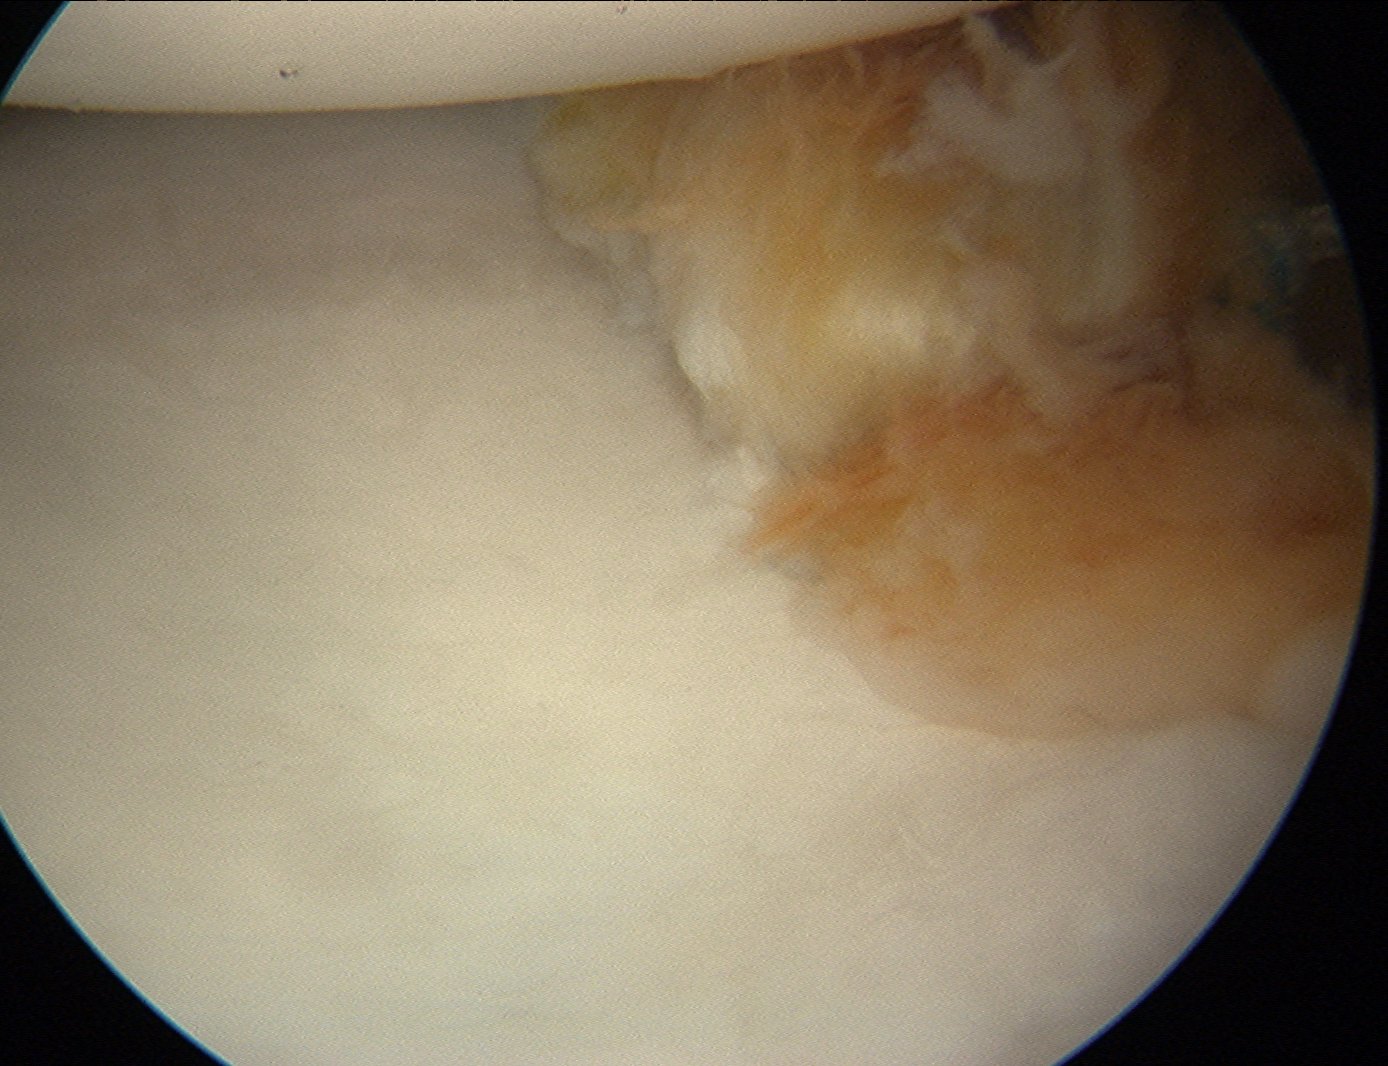

Glenohumeral joint assessment

Labrum

Anterior inferior labral tears |

SLAP tears | Posterior labral tears |

Glenoid assessment

Anterior chondral damage

Anterior glenoid bone loss

Hill Sachs lesion